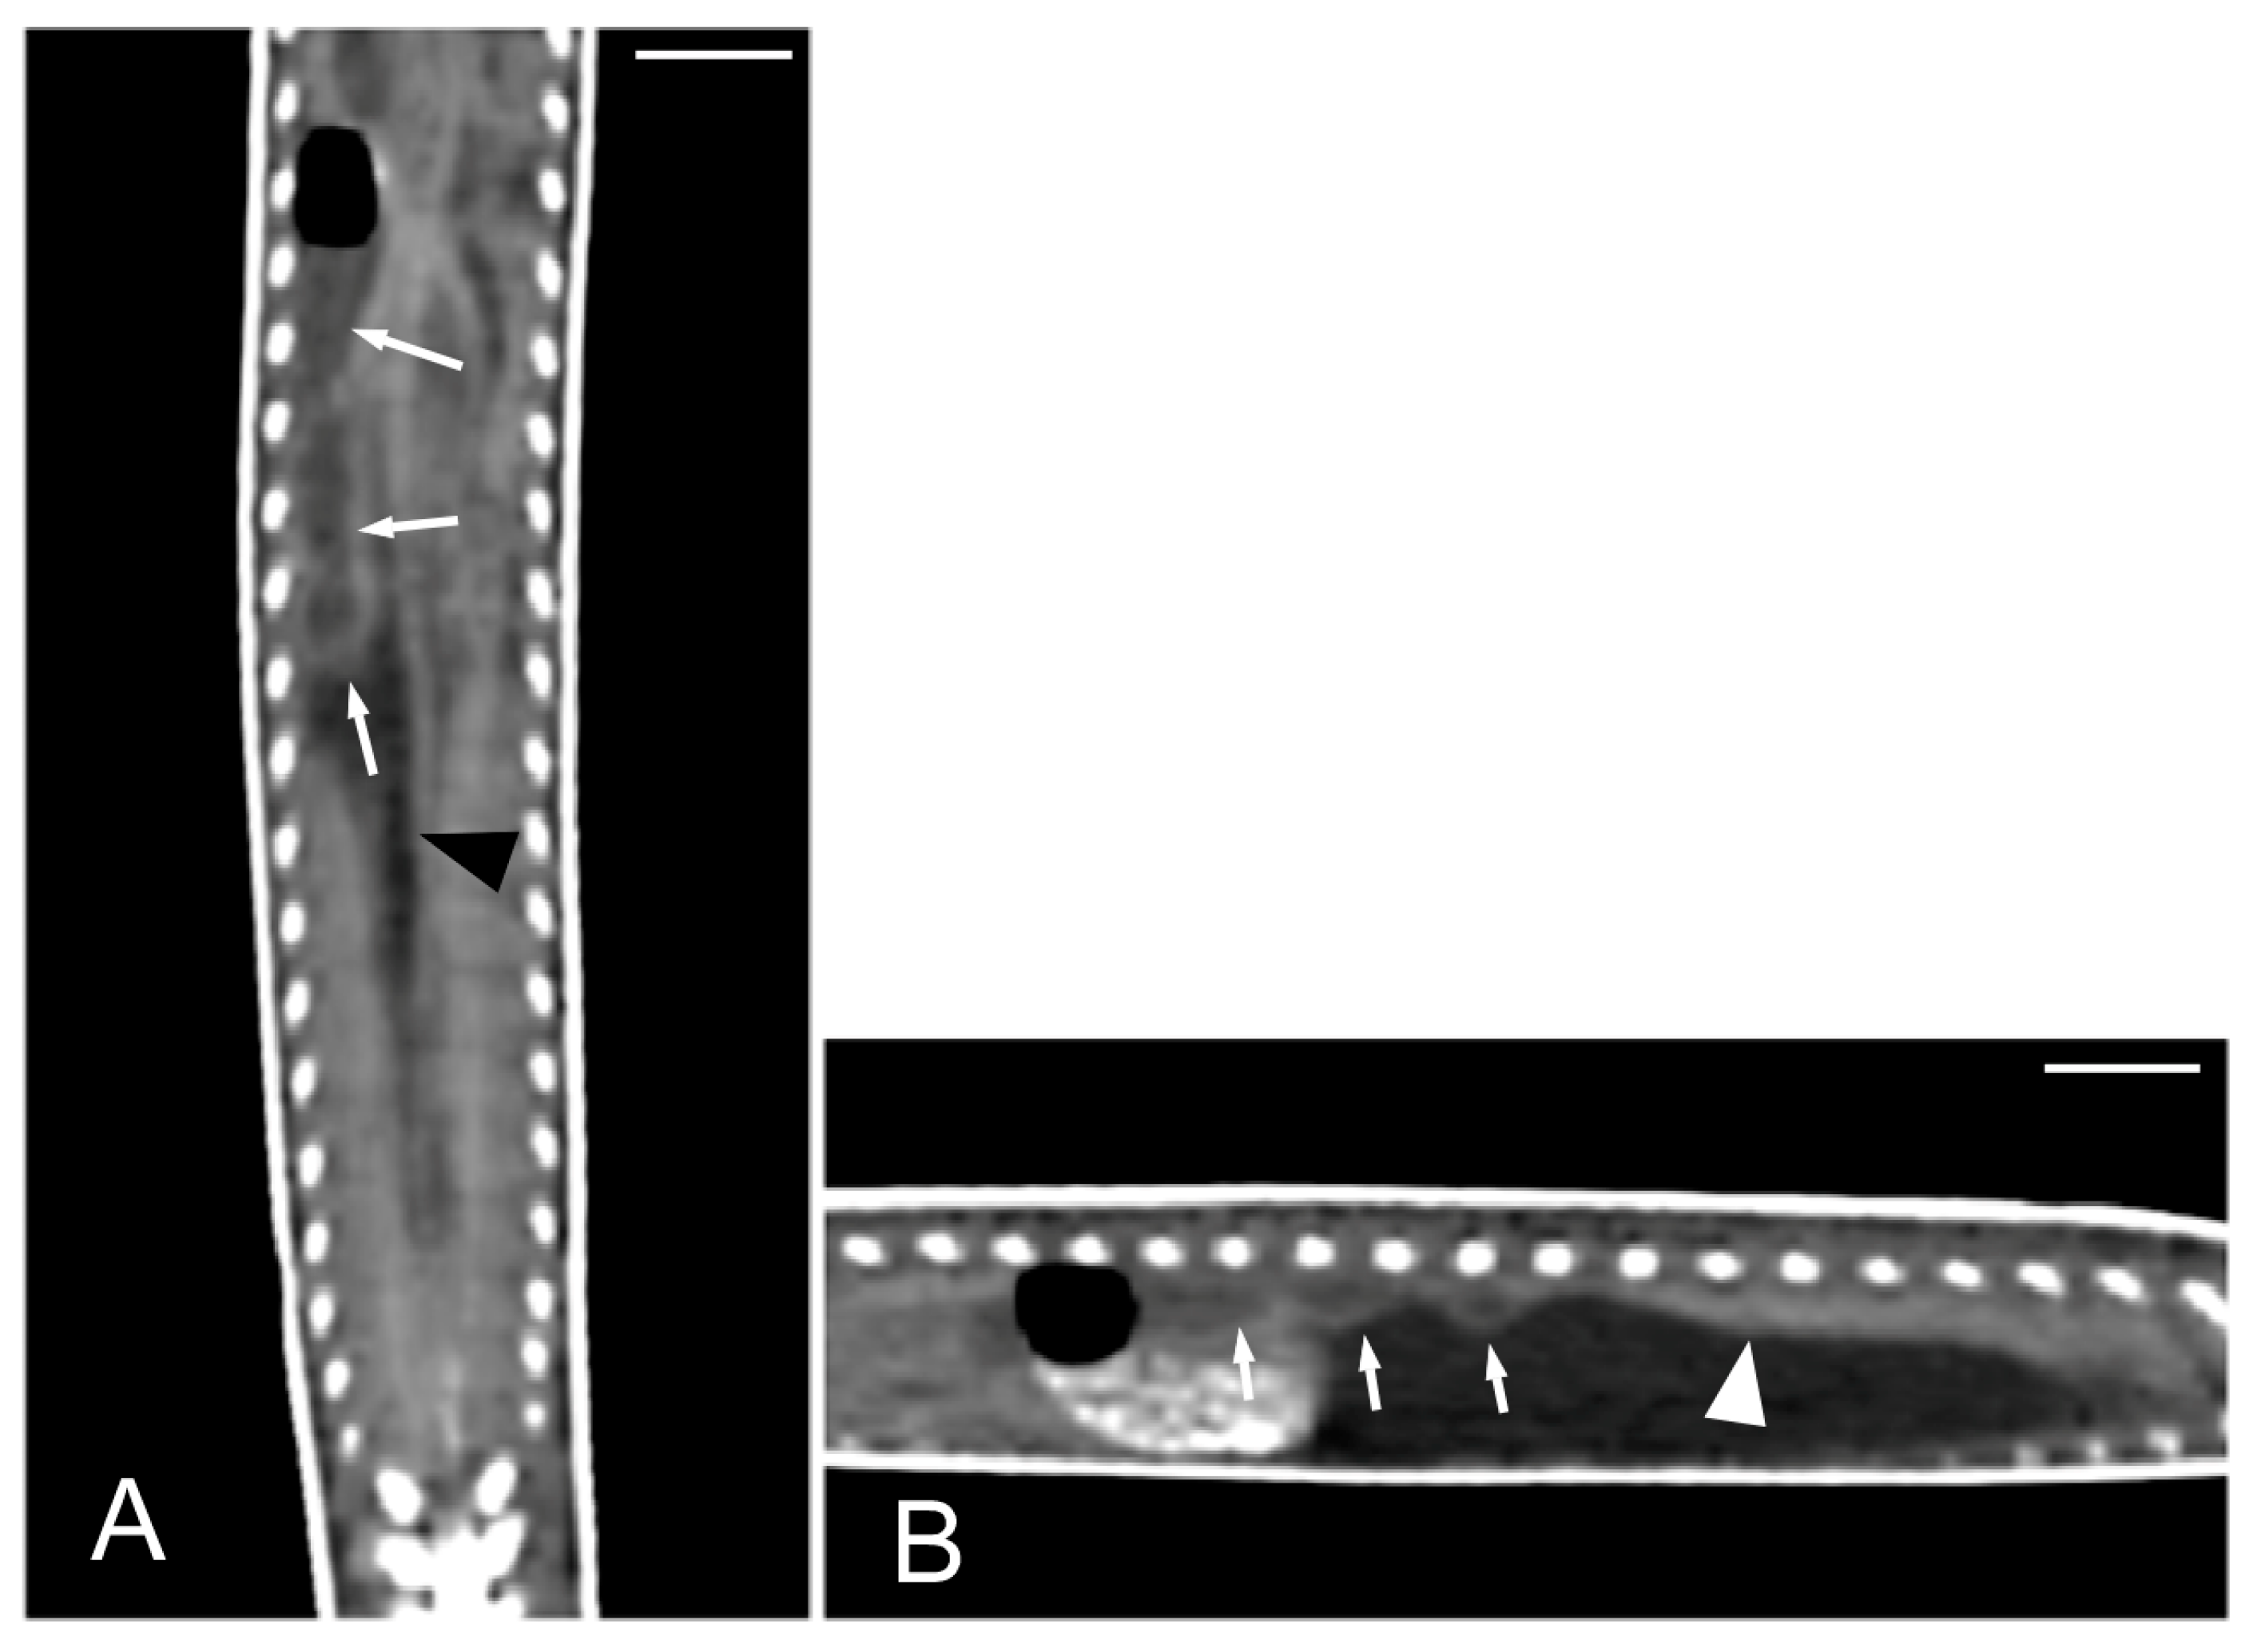

Figure 10.

The CT images of Pseudopus apodus in the sagittal (A,B), dorsal (C) and transverse (D) planes showing the liver (between arrowheads) and gallbladder (arrow). Image (A) was obtained precontrast administration and images (B–D) were obtained postcontrast. The contrast enhancement of the normal hepatic parenchyma improved the differentiation between it and the gall bladder and between the liver and stomach (S). Bar = 10 mm.

Figure 11.

The CT images of Pseudopus apodus in the dorsal plane showing segments of the esophagus (white arrowheads), stomach (black arrowheads), and intestine (white arrows) with intraluminal gas (A) and with gas and hyperattenuating content (B). Bar = 10 mm.